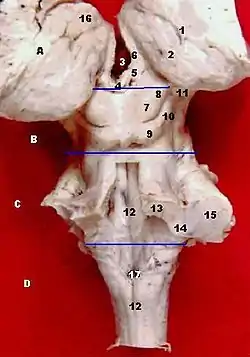

Inferior view in which the midbrain is encircled blue. | |

A:Thalamus B:Midbrain C:Pons

D:Medulla oblongata

7 and 8 are the colliculi.